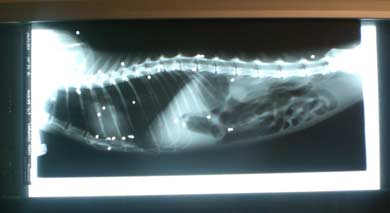

31 Kugeln im Körper!- Neurone geht

es sehr schlecht!

Neurones Allgemeinbefinden ist schlecht. Wir

hoffen er schafft es . Als der Kater untersucht

wurde, entdeckten die Tierärzte auf dem

Röntgenbild, dass Neurones Körper

mit Kugeln förmlich gespickt ist. So

viele Kugeln (bzw Teile) in einem Tier haben

sie bisher noch nicht gesehen.

Die Bluttests sind da, die Bleiwerte sind

momentan noch nicht bedenklich, dass heisst

sein momentan schlechter Zustand beruht nicht

hauptursächlich auf einer Bleivergiftung,

das ist ja schon mal was!

Allerdings besteht in Zukunft kaum die Möglichkeit

ihn von seinen Schrotkugelteilen zu befreien,

die sind zwar auf dem Röntgenbild super

zu sehen, aber man findet sie dann nicht leicht

in der Katze, dazu müsste man das ganze

Weichteil- und Muskelgewebe durchsuchen und

würde gar nicht alles finden.